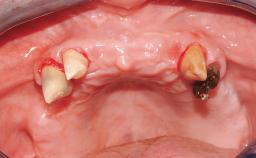

A 63-year-old male patient was referred for a consultation and treatment of partial edentulism in the maxilla. The patient presented with residual anterior teeth and declined a partial removable prosthesis. He reported that the maxillary posterior teeth had been extracted due to mobility and periodontal disease two months before the consultation. The patient’s chief complaint was that his residual maxillary teeth were mobile and that he was unable to chew. The patient’s desire was a stable and comfortable fixed maxillary rehabilitation. The patient was a light smoker (fewer than 10 cigarettes/ day), and his medical history was without significant findings. He was not on any regular medication at the time of consultation. The extraoral examination revealed a normal physiognomy with a correct distribution of the facial thirds. The patient presented a low lip line, and the transition line between teeth and soft tissues was not exposed during a forced smile.

Periodontal Status History of periodontitis or genetic predisposition